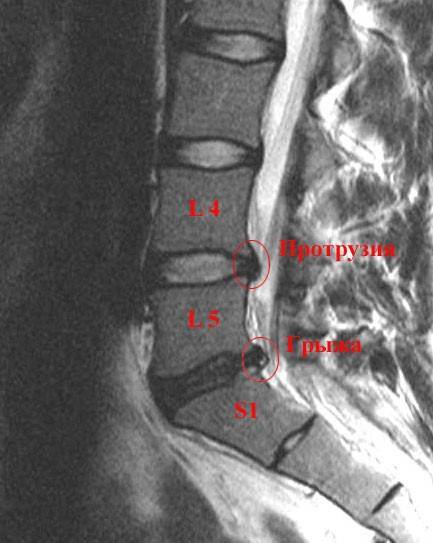

Таким образом, для начала формирования грыжи диска требуется предварительное ослабление фиброзного кольца с появлением в нем надрывов волокон. Поскольку грыжа − процесс локальный, чаще всего располагающийся в задних отделах диска, для ее формирования мало наличия повышения внутридискового давления, нужно чтобы повышенное давление действовало ассиметрично. В противном случае вместо формирование грыжи, у людей чаще бы развивалось состояние упомянутое выше — bulging disc (выпуклый диск). Однако грыжи встречаются гораздо чаще. Это связано с тем, что как эндогенные, так и экзогенные факторы, являющиеся причиной формирования остеохондроза, а в последующем и грыжи диска, действуют, как правило, ассиметрично, перегружая задние отделы дисков. Так при сидячей работе почти всегда имеется сглаживание шейного и поясничного лордоза или даже их кифозирование и усиление грудного кифоза, что способствует устремлению внутридискового давления в заднем направлении и перерастяжению волокон задних отделов фиброзного кольца. Если бы данный механизм был единственным, то мы в большинстве бы случаев имели локальные срединные или диффузные грыжи. Однако грыжи чаще всего имеют сторонность и локальный характер виду того, что у подавляющего большинства пациентов присутствует эндогенный фактор повышения внутридискового давления в виде функциональных блоков. Они, в результате создания ассиметричного положения позвонка, способствуют тому что вектор повышенного внутридискового давления имеет определенное направление, перегружая, как правило, не всю заднюю полуокружность диска, а какую-то ее часть. В результате волокна фиброзного кольца в одном из мест перерастягиваются в большей степени, далее в них формируется трещина, которая становится самым слабым местом диска и в нее внедряется пульпозное ядро, выдавливающее в последующем наружные отделы фиброзного кольца за пределы анатомических границ диска. Так формируется первая стадия грыжи диска — протрузия. В последующем разрыв углубляется и фиброзное кольцо разрывается полностью. Часть пульпозное ядра выходит за пределы фиброзного кольца под заднюю продольную связку, которая прикрывает задние отделы диска. Это вторая стадия грыжи диска, носящая название сублигаментарная экструзия. В последующем задняя продольная связка может разрываться и тогда пульпозное ядро выходит за пределы связки. Эта третья стадия грыжи диска, называющаяся транслигаментарная экструзия. Далее, если выпавший фрагмент пульпозного ядра отделяется от его материнской части, грыжа переходит в четвертую стадию — транслигаментарная секвестрация.